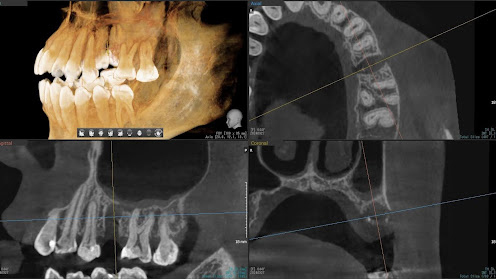

2.右上6番の上顎既存骨2mmのグラフトレスサイナスリフト(骨補填剤を使わない上顎洞挙上術)のケース

Before

枚方市のインプラントの症例

K・Y 様 女性 50代

症状としては、右上6番の歯が歯周病のため、自然に抜けてしまった。

治療法としては、歯周病により、右側6番の上顎骨が吸収して、2mm程度の骨しか残っていなかったため、サイナスリフトが必要であった。通常のサイナスリフトだと時間(時間的には1年から1年半程度かかると考えます。)と費用がかかり、患者様への時間的、肉体的、金銭的負担が大きくなることを考慮して、今回は、インプラントの種類としては、エクストラワイドショートインプラント、術式としては、デンサーバーを使用したグラフトレスサイナスリフトを選択しました。最終補綴物はジルコニアで仕上げています。

結果としては、高度に吸収した上顎骨に対するインプラント治療であったが、グラフトレスサイナスリフトを行うことで、短時間(2か月半程度)で治療を終えることができた。また、サイナスリフトによくある術後合併症である上顎洞炎を起こすことなく、患者様への肉体的な負担を抑えた治療を行うことができた。また、上顎右側6番にインプラント治療できたことにより、咬合が安定するとともに、歯周病にり患している上顎の他の歯に対する負担を少なくすることができた。

治療の期間・回数:約2か月半、6回

治療の価格:363,000円(税込)

治療費の内訳:インプラント基本料(フィックスチャー及び手術費用、投薬費用、レントゲン費用、インプラント上部費用(アバットメントおよびジルコニアクラウンの費用用)330000円(税込み)オプション費用グラフトレスサイナスリフト費用 33000円(税込み)

治療のリスクや副作用:手術後に、痛みや腫れ、出血、合併症などを引き起こす可能性があります。噛む感覚がご自身の歯と異なる場合があります。見た目がご自身の歯と異なる場合があります。手術後にメインテナンスを継続しないと、インプラントが抜け落ちる可能性があります。